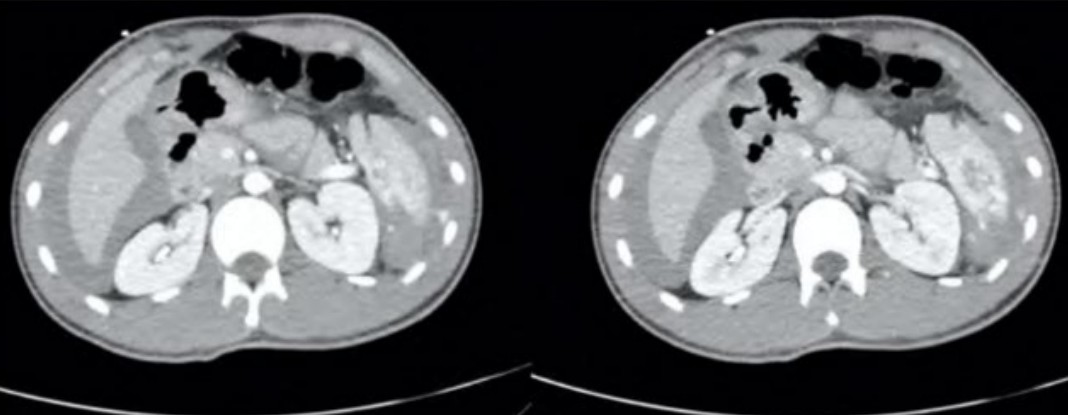

Blunt abdominal trauma

A 28-year-old man is brought into your tertiary ED having been witnessed to jump from a 2nd storey balcony (approximately …